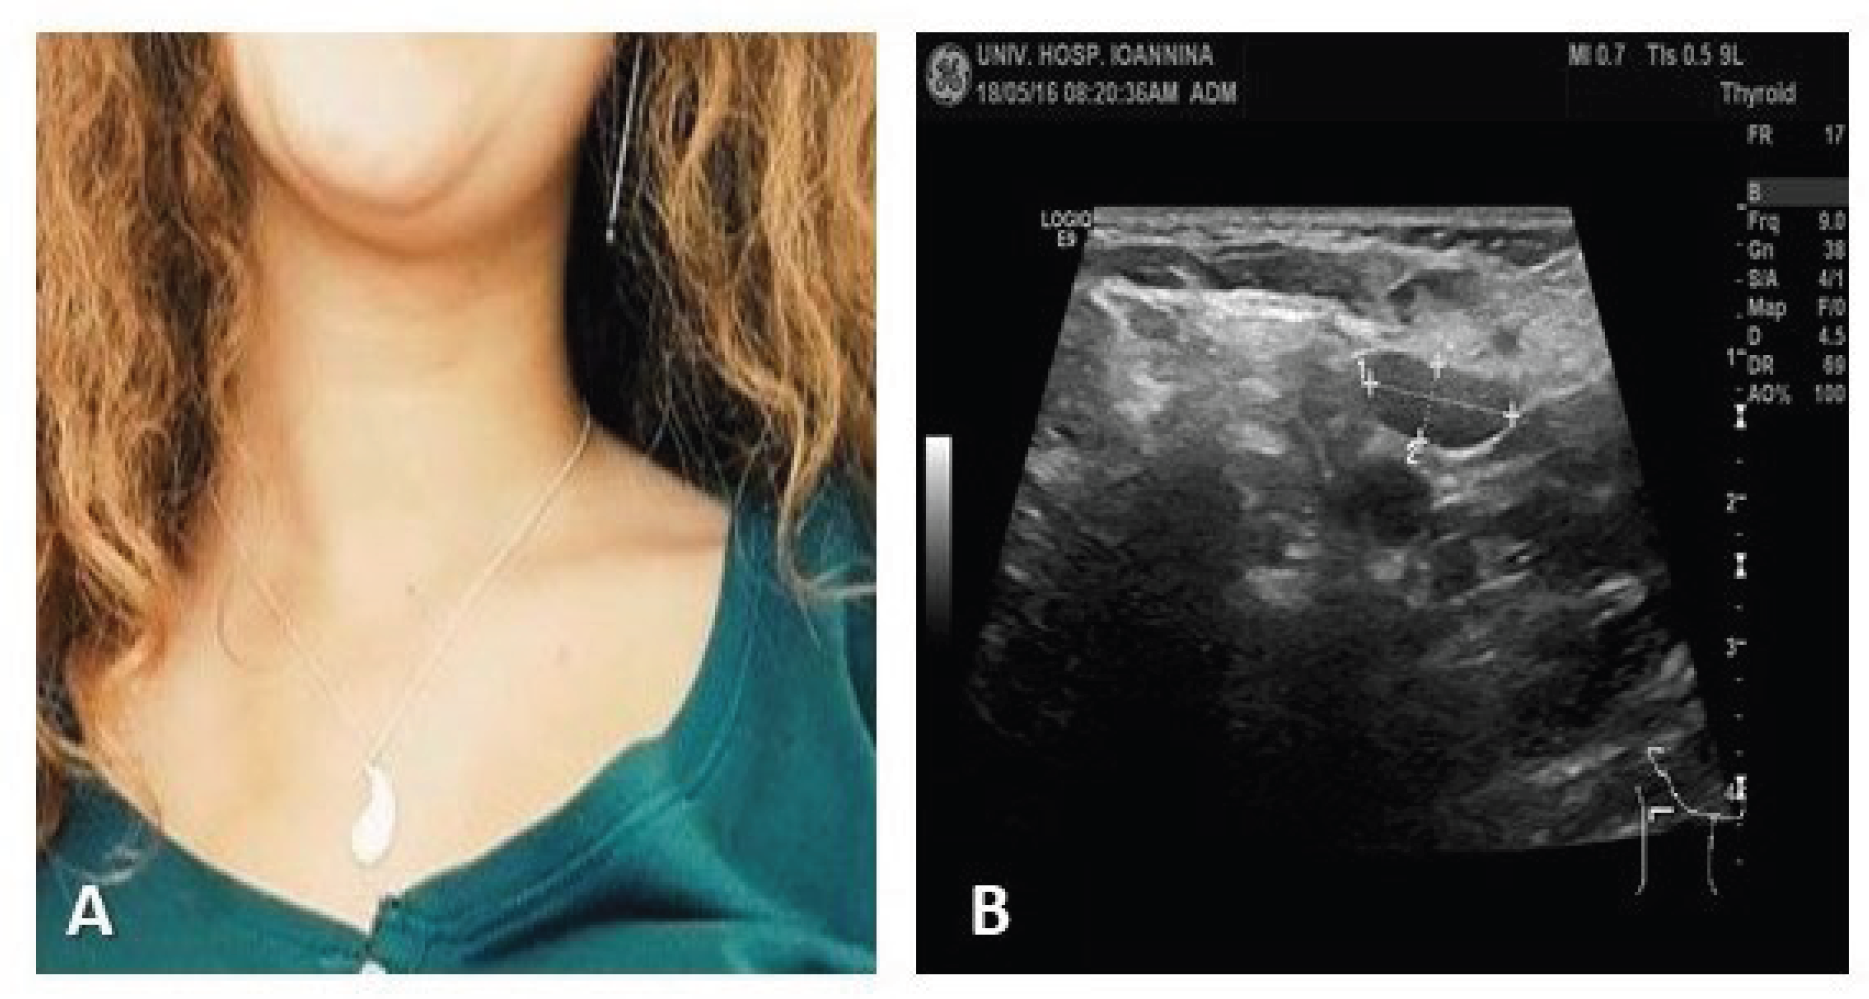

On physical examination, she had fever 38.5°C, she was quite pale but in good general condition; lymphadenopathy was identified in inspection (Figure 1) of cervical and supraclavicular lymph nodes. In palpation: lateral cervical lymph nodes, the largest ~3 cm, hard, mobile and moderately painful. The smaller lymph nodes were mobile and painless. The supraclavicular lymph nodes both mainly on the right, painless on palpation, non-mobile, hard; the small axillary nodes were barely palpable. Other lymph node groups were not palpable. Examination of the other systems was unremarkable, and the abdomen was without organomegaly.

Figure 1. Cervical and Supraclavicular lymphadenopathy.